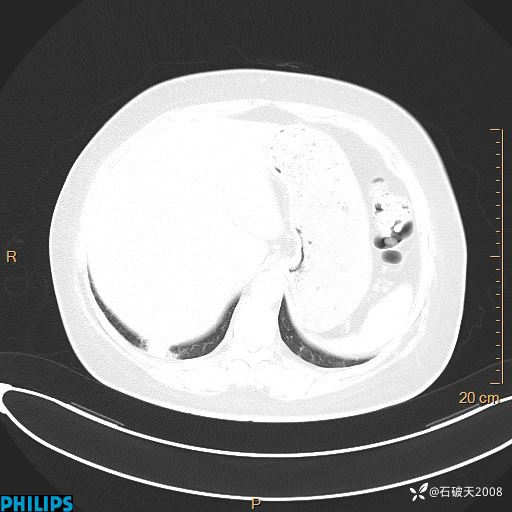

动脉期